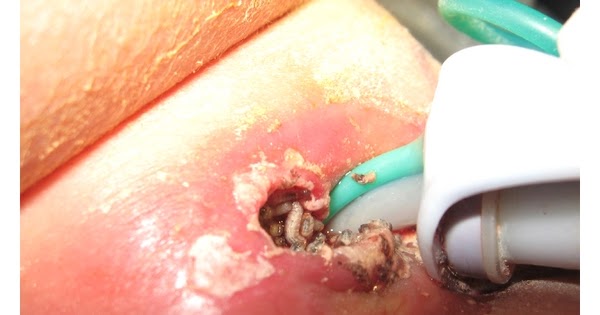

Myiasis in Basosquamous Carcinoma - YouTube

Myiasis in Basosquamous Carcinoma - YouTube from i.ytimg.com

Myiasis is the parasitic infestation of the body of a live animal by fly larvae (maggots) which grow inside the host while feeding on its tissue mya. Myasis—by this term (spelled also myiasis, and myiosis), is meant parasitism by dipterous larv.